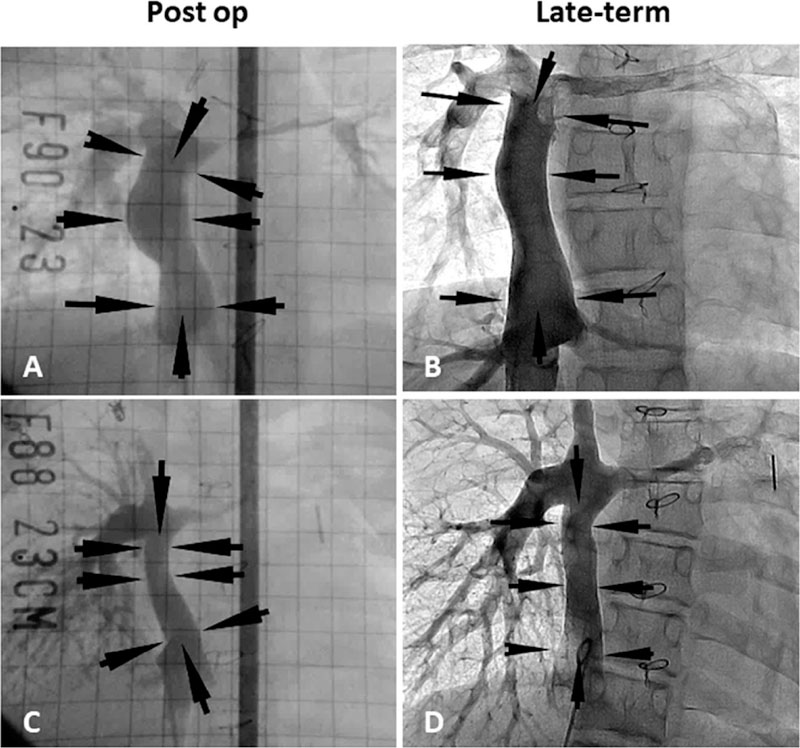

Between September 2001 and December 2004, 25 Japanese patients underwent extracardiac total cavopulmonary connection (TCPC) operations with a TEVG [59]. Patient demographics, diagnosis, graft type, and size at the time of implantation are presented in Table 1. The median patient age at the time of operation and mean follow-up time was 5.5 and 11.1 years, respectively [60,61]. There were no incidences of graft-rupture, aneurysmal formation, or ectopic calcification. While eight patients died within the follow-up period, none of the mortalities were due to graft-related complications. In fact, the autopsy of one patient who died 13 years after TEVG implantation revealed a structure similar to that of a native vein or pulmonary artery (Figure 3) [62]. However, seven patients presented with asymptomatic graft stenosis and underwent successful balloon angioplasty, including one that required a repeat catheterization and stent placement. Additionally, one patient’s TEVG had a thrombus formation one year after implantation, but this was successfully resolved with anticoagulation drug therapy. When contacted, all surviving patients reported no functional limitations (Figure 4) [61].

Figure 3.

Postoperative and late-term TEVG angiography. (A) Postoperative angiography in patient 22. (B) Angiography 11 years after implantation in patient 22. (C) Postoperative angiography in patient 23. (D) Angiography eight years after implantation in patient: 23. Arrows indicate the TEVG location. Angiography shows macroscopic growth of the TEVGs. Adopted with permission front Shinoka et al.